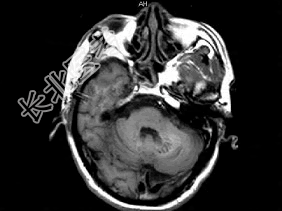

- 单项选择题男,49岁, 反复发作性癫痫,双手震颤5年, 伴头昏行走不稳,生化检查: 血清钙降低,血清磷升高, 请根据所提供图像,选择最可能的诊断 ( )

A、Fahr病

B、一氧化碳中毒性脑病

C、霉变甘蔗中毒

D、肝豆状核变性

E、甲旁低